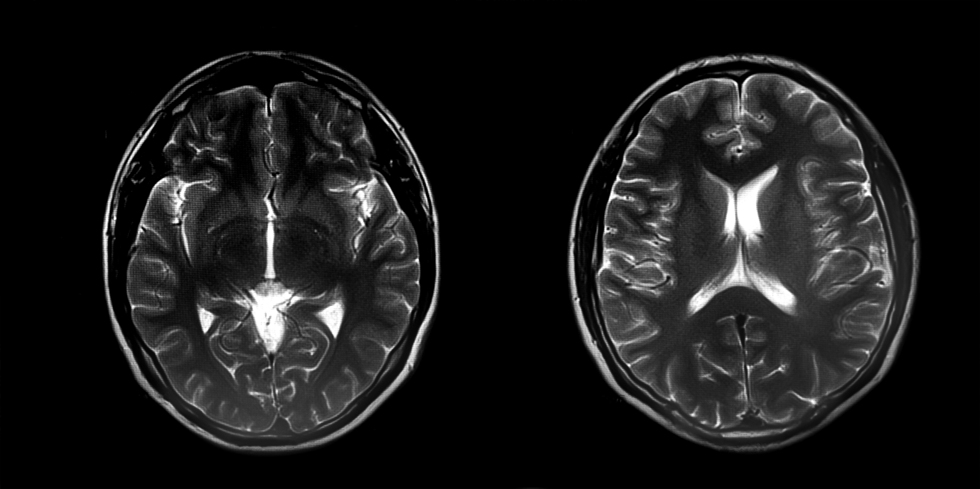

Eleven of 154 patients who underwent CSF JCV qPCR testing had a positive result (7 %). Median age was 60 years (range: 33–79 years) and 7/11 (64 %) were male. Nine of 11 (82 %) were overtly immunocompromised. Five of 11 (45 %) had a viral load below the lowest quantifiable standard (<4290 copies/ml). All had a clinico-radiographic presentation compatible with PML and no more likely alternative diagnosis, resulting in a PPV of 100 %. All had one or more suggestive neuroimaging findings that supported PML diagnosis (Milky Way sign/punctate pattern, 9; rim-and-core pattern, 7; T2/FLAIR mismatch, 6; shrimp sign, 4; SWI-hypointense rim, 2; across-the-pons sign, 1; barbell sign, 1).